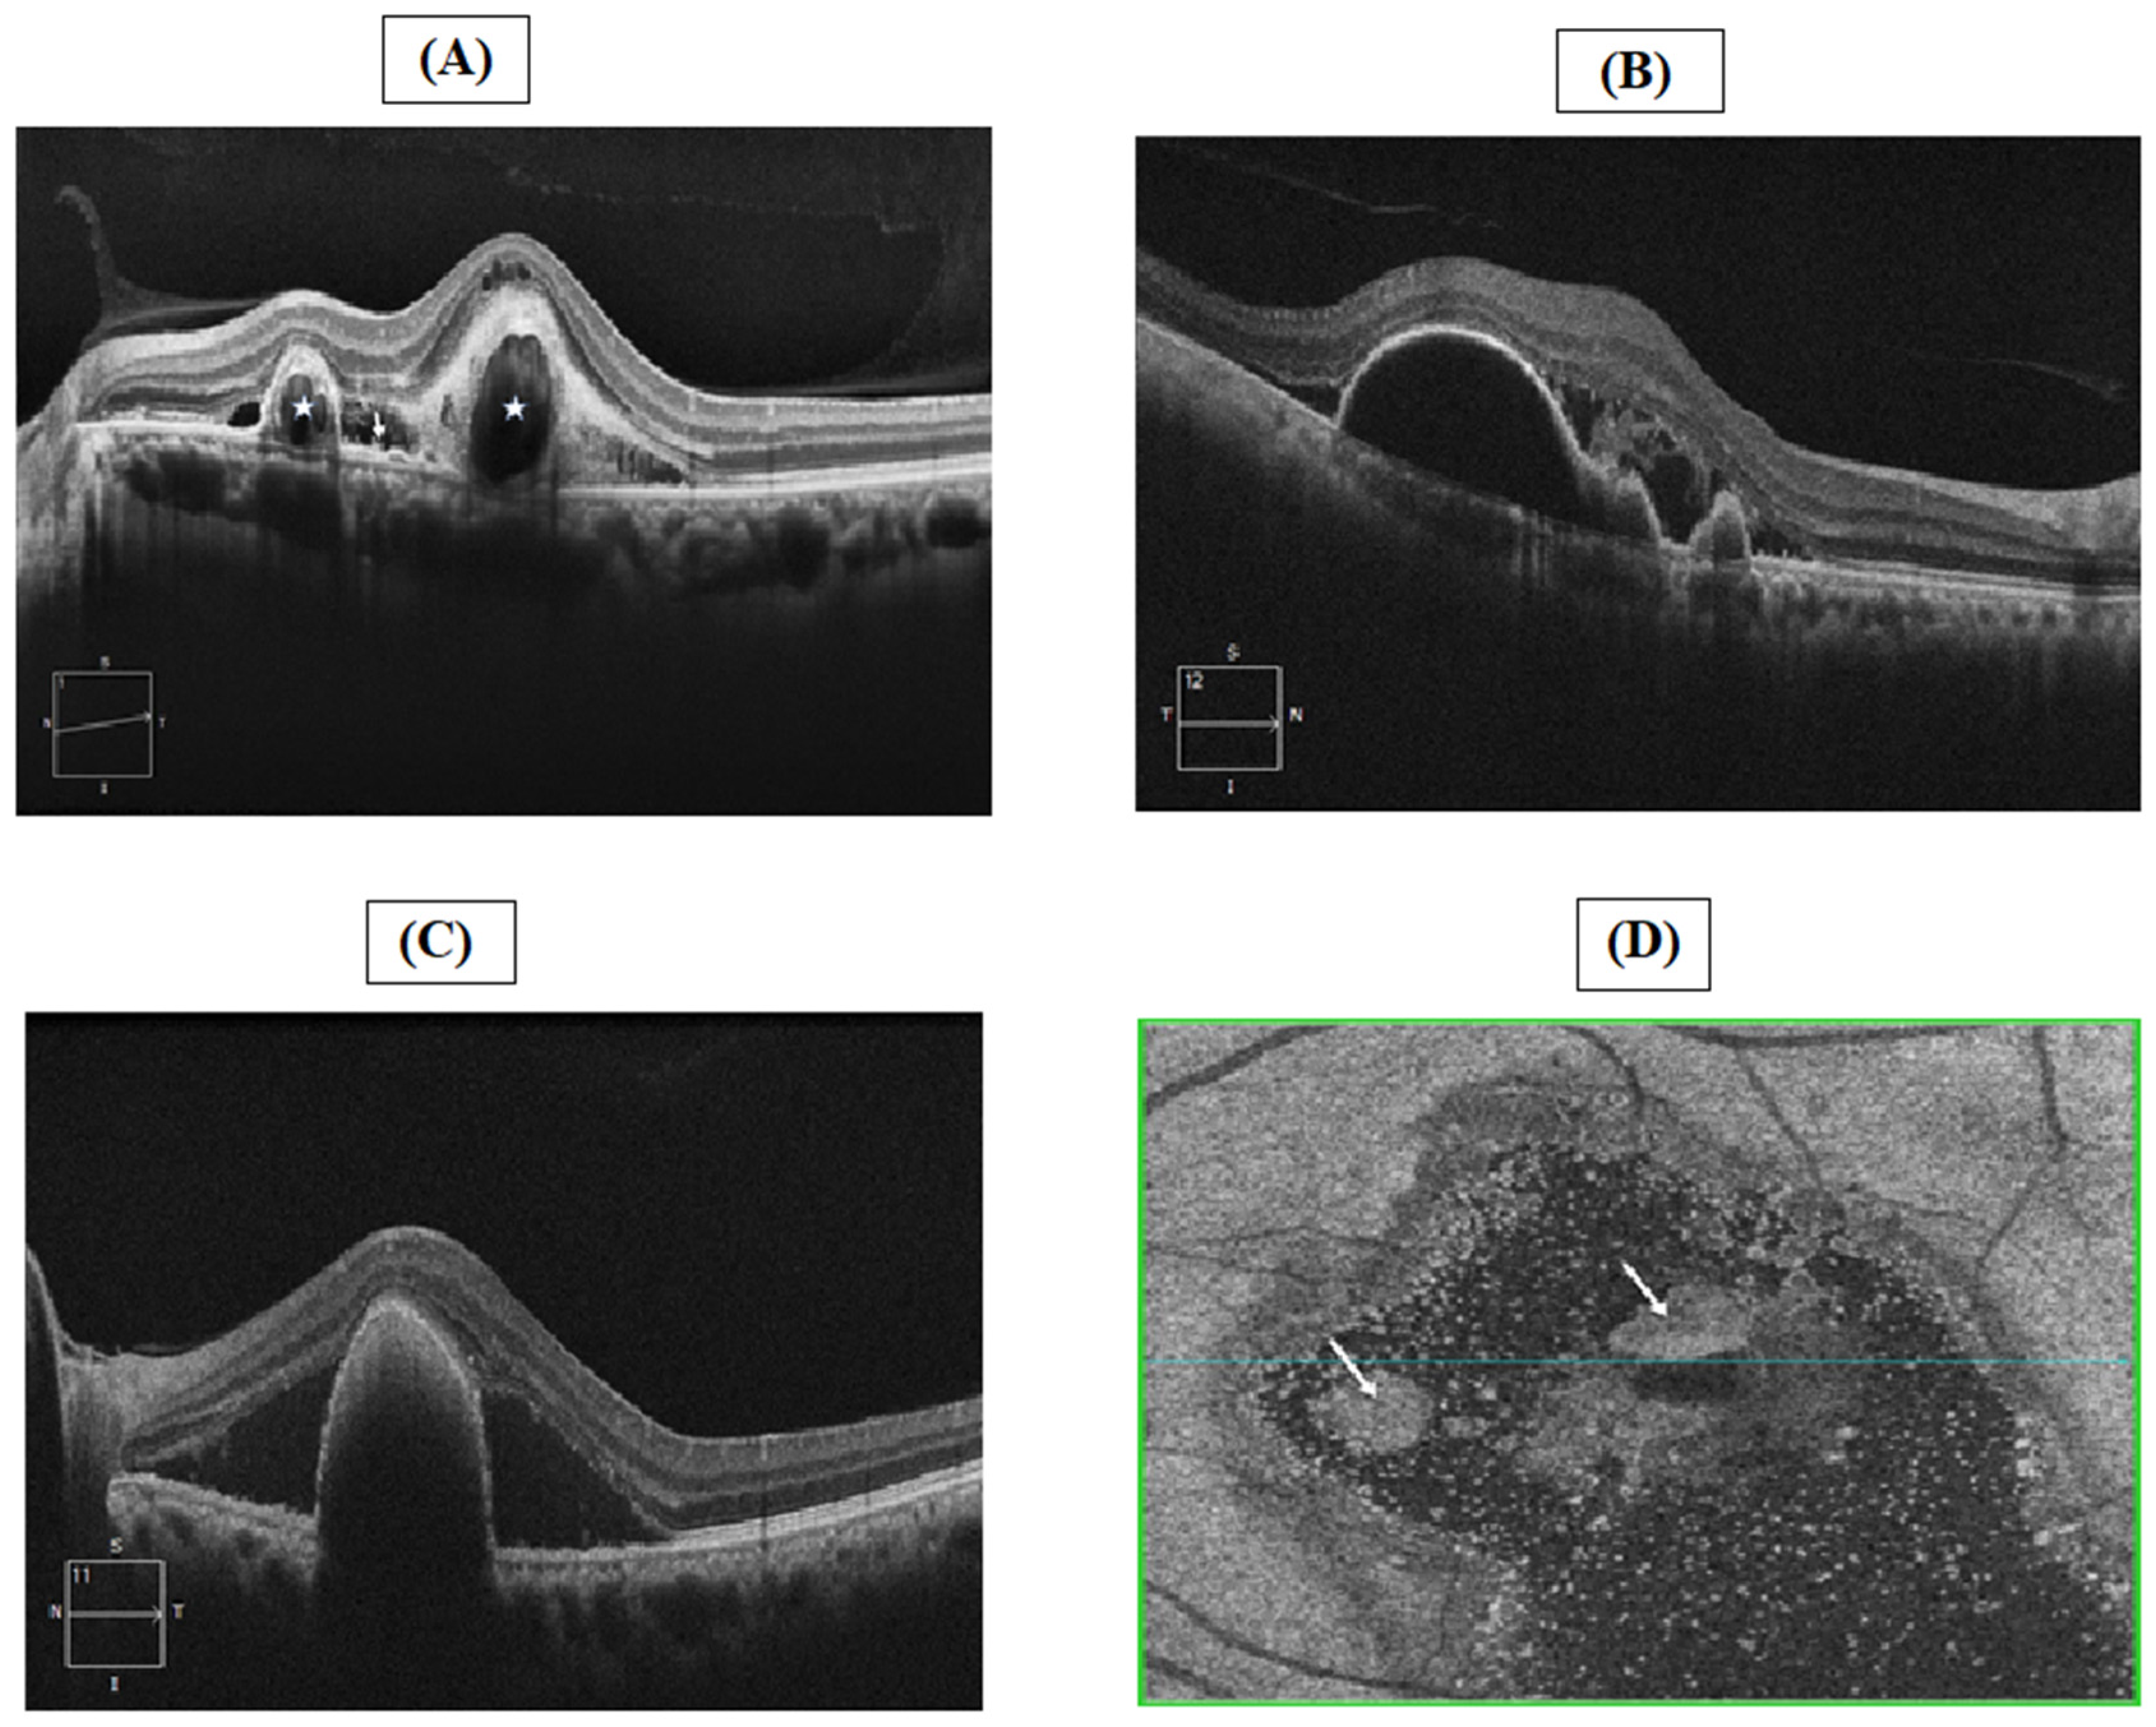

4.4. Optical Coherence Tomography

- Teo, K.Y.C.; Cheung, G.C.M. New Concepts in Polypoidal Choroidal Vasculopathy Imaging: A Focus on Optical Coherence Tomography and Optical Coherence Tomography Angiography. Asia Pac. J. Ophthalmol. 2019, 8, 165–171. [Google Scholar] [CrossRef]

- Permadi, A.C.; Djatikusumo, A.; Adriono, G.A. Optical coherence tomography in diagnosing polypoidal choroidal vasculopathy. Looking into the future: A systematic review and meta-analysis. Int. J. Retin. Vitr. 2022, 8, 14. [Google Scholar] [CrossRef]

- Liu, R.; Li, J.; Li, Z.; Yu, S.; Yang, Y.; Yan, H.; Zeng, J.; Tang, S.; Ding, X. Distinguishing polypodal choroidal vasculopathy from typical neovascular age-related macular degeneration based on spectral domain optical coherence tomography. Retina 2016, 36, 778–786. [Google Scholar] [CrossRef]

- Lau, T.; Wong, I.Y.; Iu, L.; Chhablani, J.; Yong, T.; Hideki, K.; Lee, J.; Wong, R. En-face optical coherence tomography in the diagnosis and management of age-related macular degeneration and polypoidal choroidal vasculopathy. Indian J. Ophthalmol. 2015, 63, 378–383. [Google Scholar] [CrossRef] [Green Version]